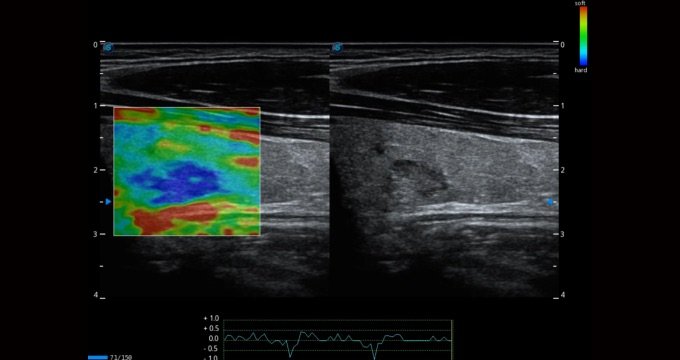

C-xlasto Bildgebung

Die C-xlasto Bildgebung erlaubt eine umfassende quantitative Elastizitätsanalyse, bei der das System schnell das Dehnungsverhältnis berechnet und ungewöhnlich harte oder weiche Veränderungen im Weichteilgewebe anzeigt. Gleichzeitig wird die Funktion durch mehrere Schallköpfe unterstützt, was hochgradig konsistente, quantitative Elastizitätsergebnisse mit guter Reproduzierbarkeit sicherstellt.